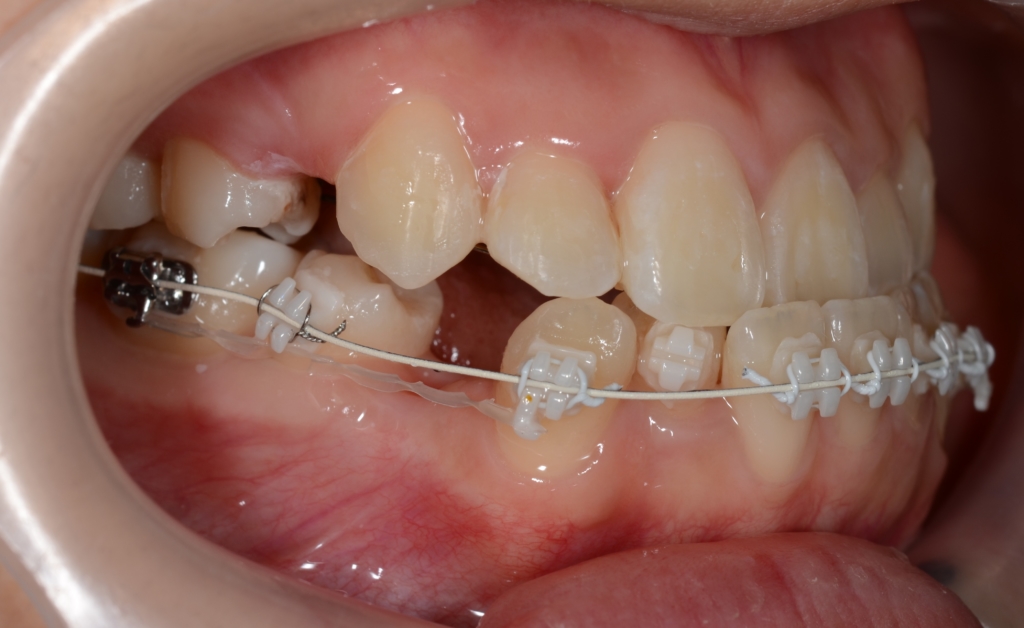

マルチブラケットシステム(ハーフリンガル type)で矯正を開始。

途中、早期の被蓋改善を図るため、上の奥歯から下の前歯へ引っ掛ける顎間ゴムを3か月間使用しています。

【1年経過】